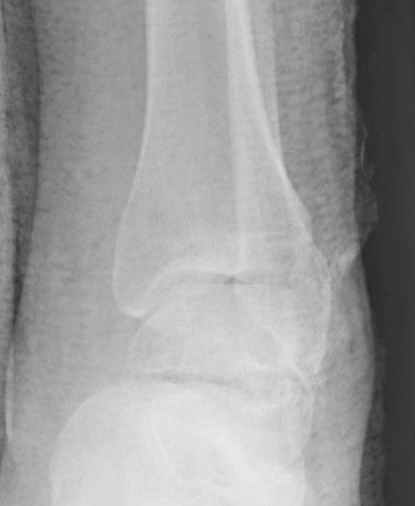

Уважаемые участники русского Ортофорума, поздравляю всех со всеми прошедшими праздниками: Новым годом, Рождеством, Hanukkah, Kwanzaa, желаю участникам всего наилучшего и здоровья.Повреждение таранной кости.Больной 81г автоавария, повреждение таранной кости, здесь снимки. Какие рекомендации?Djoldas Kuldjanov, MDDepartment of Orthopedic SurgerySt. Louis University Medical Center

Вообще то мало данных: торчит ли осколок под кожей, сопутствующая паталогия (атеросклероз, диабет), сколько времени прошло после травмы? Я думаю, что в данном случае можно ограничиться или небольшим вмешательством вплоть до удаления дистального отломка из небольшого разреза, или наложением аппарата с дистракцией переднего отдела стопы в эквинусе, может быть удастся этот отломок и вправить. Опорная функция в любом случае должна сохраниться при любом варианте лечения, не думаю что будет страдать кровоснабжение таранной кости. Я когда то удалил дистальную половину таранной кости, с последующим анкилозированием в тарано-ладьевидном суставе, хотя более опытные товарищи советовали провести астрагалэктомию, но тем не менее тогда результат оказался хороший. Конечно объязательно назначение препаратов улучшающих микроциркуляцию, противоотечная терапия и т.п. Удачи.

В декабре у меня был пациент с политравмой и аналогичным повреждением тарана с подвывихом в таранно- ладьевидном суставе, единственное отличие - отломок головки тарана был меньше по размеру и фрагментирован, поэтому его фиксация была невозможна.

Для доступа к задне-медиальному суставному фрагменту я выполнил косую остеотомию внутренней лодыжки у её основания -получается хороший доступ к голеностопу, адекватный обзор и возможность восстановить суставную поверхность. фрагмент фиксировал двумя 3,5 мм спонгиозными винтами с неполной резьбой, *утопив* головки винтов в кость. Аналогичная фиксация и двумя тягловыми винтами и внутренней лодыжки. \в качестве альтернативы для

фиксации фрагмента тарана можно было бы использовать и герберт винты, но по организационным причинам :-(( набора не оказалось под рукой).

Вывих в таранно-ладьевидном суставе удалось вправить с помощью Howard retractor, используя его в качестве рычага.Сегодня искал в рентген архиве